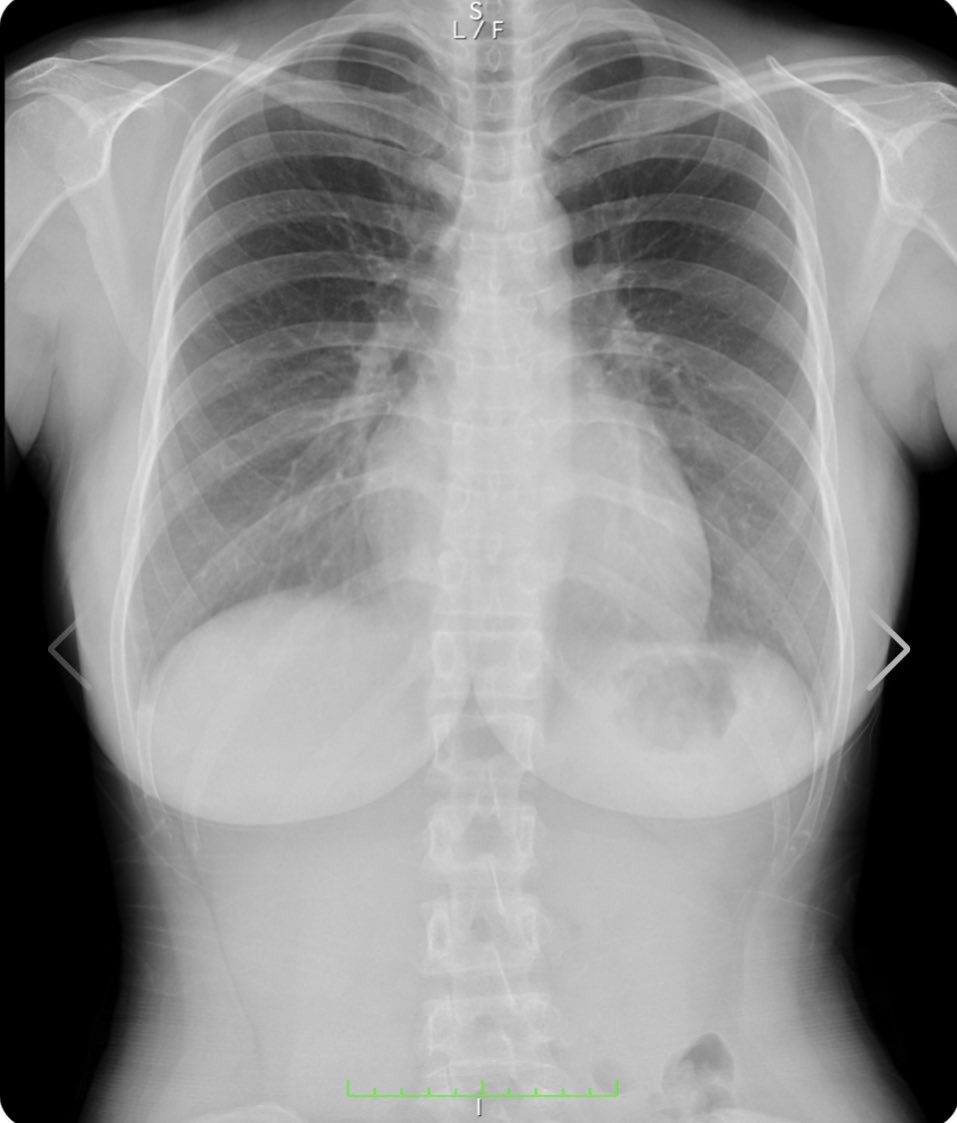

沒看過這麼露骨的照片!日本寫真女星天木じゅん(天木純),一張可愛臉蛋配上核彈級I罩杯巨乳,身高還只有149公分,是公認的「童顏巨乳教主」,最近她在推特上分享了自己的胸部X光照,因為去年8月確診了新冠肺炎,健檢時也拍了X光片檢查自己肺部狀態,順便曬了曬自己的巨乳內可沒有任何填充物,是貨真價實的純天然!

從天木じゅん的X光片中可以隱約看出胸部的線條,飽滿渾圓非常性感(?)她表示畫面中右胸的陰影是胃泡,自己的健康無虞,讓粉絲不需要擔心,而自己的不科學乳量則是遺傳的關係,絕對沒有人工的痕跡,敢這樣大動作澄清,不愧是擁有「天乳」的天木じゅん。